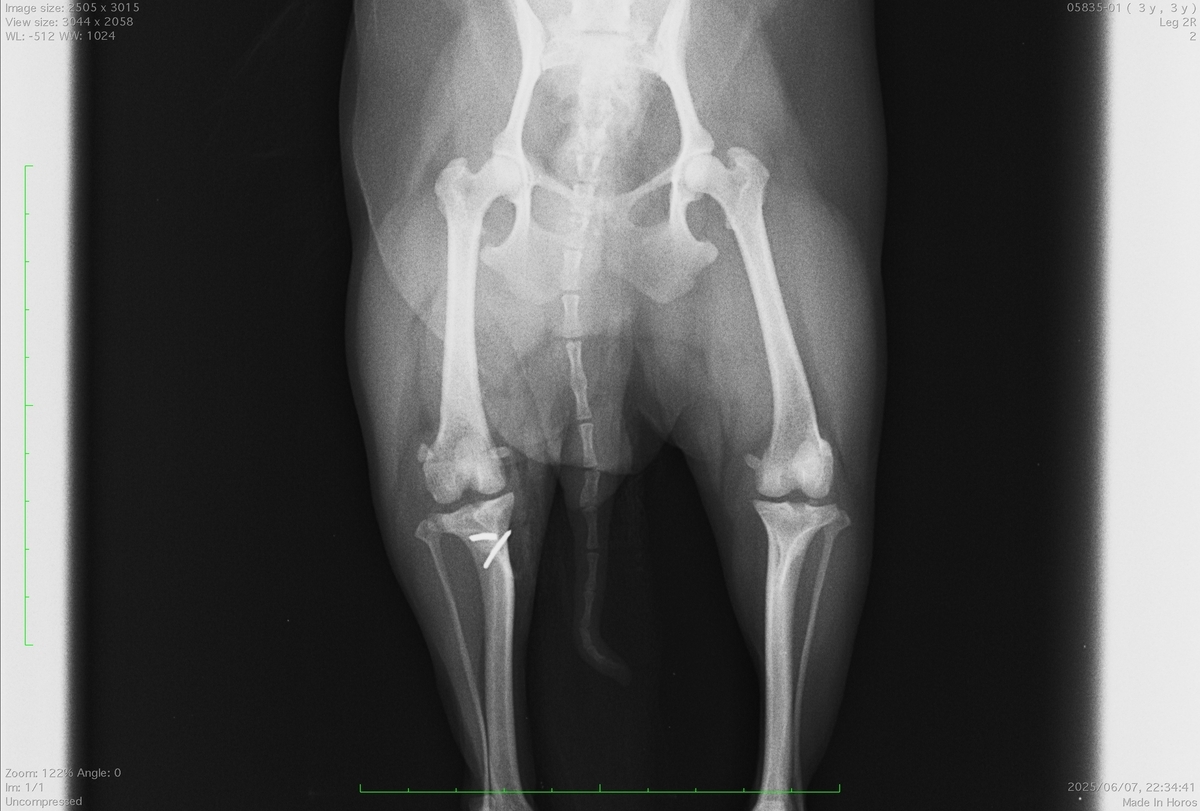

9歳の雑種犬(チワワ×プードル)で左後肢の跛行で来院されました。

触診とレントゲン写真で前十字靭帯断裂と診断しました。

左後肢の脛の骨が右足と比べて前方に変位しているのがわかります。